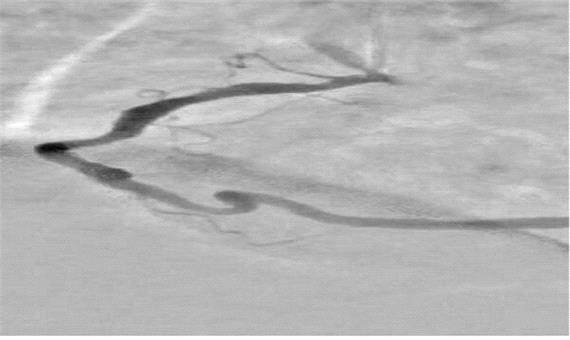

آخوندی با اشاره به دلایل انتخاب این تحقیق، توضیح داد: در آنژیوگرافی قلب، تداخل سایه‌های ناشی از بافت‌ها و استخوان‌های قفسه سینه و همچنین حرکات تنفسی و ضربان قلب باعث می‌شود تشخیص دقیق عروق کرونری دشوار شود. این مسئله منجر به نیاز به تزریق بیشتر ماده حاجب و دریافت دوز بالاتر اشعه توسط بیمار می‌شود.

وی بخش نوآورانه طرح را شامل استفاده از شبکه‌ خودرمزگذار هدایت‌شده برای بازسازی پس‌زمینه تصاویر حاوی ماده‌ حاجب از تصاویر بدون ماده حاجب ذکر کرد و افزود: همچنین در طراحی شبکه‌های عصبی عمیق متناسب بودن با تصاویر آنژیوگرافی به‌علت مقیاس خاکستری آنها و ظرافت عروق در طراحی لحاظ شده‌است.

آخوندی ویژگی‌های این طرح را شامل افزایش وضوح عروق کرونری در تصاویر آنژیوگرافی، کاهش نیاز به تزریق مقدار زیاد ماده حاجب و در نتیجه کاهش خطرات مرتبط با آن برای بیمار دانست و افزود: همچنین نسبت به روش‌های سنتی، زمان پردازش تصاویر را به طور قابل توجهی کاهش می‌دهد و می‌تواند حتی با در اختیار داشتن یک تصویر تکی حاوی ماده حاجب نیز عمل اصلاح و پردازش را انجام دهد. در نهایت، بهره‌گیری از فناوری شبکه‌های عصبی عمیق، امکان استخراج و بازسازی هوشمند پس‌زمینه و جداسازی بهتر عروق را فراهم می‌کند و طرح را از نظر علمی و کاربردی در سطح روش‌های نوین پردازش تصویر پزشکی قرار می‌دهد.